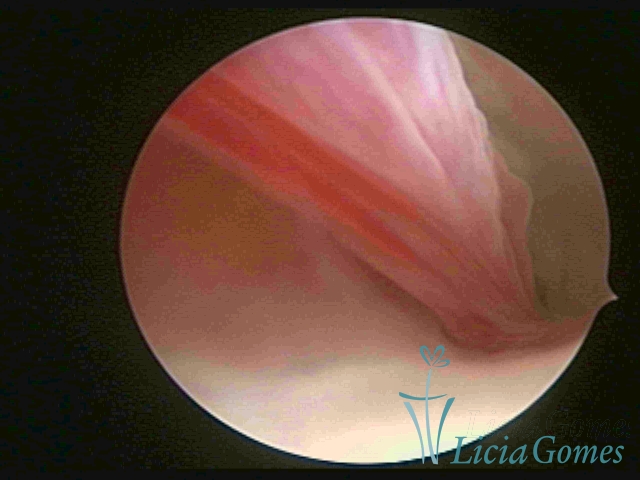

PÓLIPOS ENDOCERVICAIS

São tumores benignos, resultantes da proliferação focal reativa aos processos inflamatórios ou à situações de hiperestrogenismo, e podem ter sésseis (com a base de implantação larga) ou pediculados do epitélio.